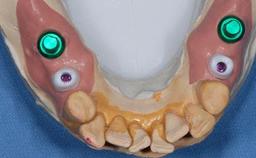

Abutment Type Customized

Prosthesis Type FDP

Retention Cemented, with meso-structure Cemented, with meso-structure

Provisional Implant-Supported Prosthesis Prosthodontic margin > 3 mm apical to mucosal margin Prosthodontic margin > 3 mm apical to mucosal margin